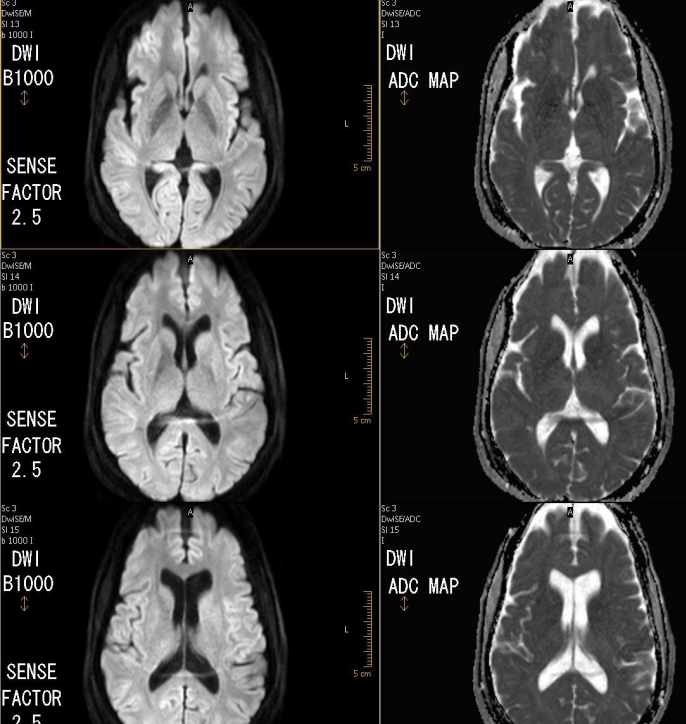

parallel imaging artifacts in DWI look like

reduce the susceptibility effects in diffusion weighted images, especially around air-tissue interfaces